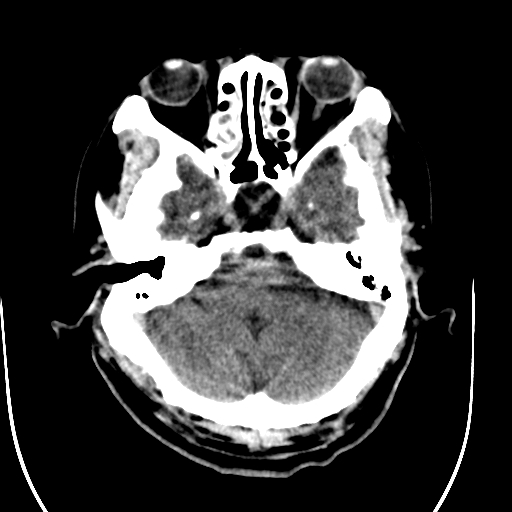

标题: CT28335:男,58岁,请各位看看是不是有脑积水,蝶窦内高密 [打印本页]

标题: CT28335:男,58岁,请各位看看是不是有脑积水,蝶窦内高密

1)脑积水。2)副鼻窦炎。